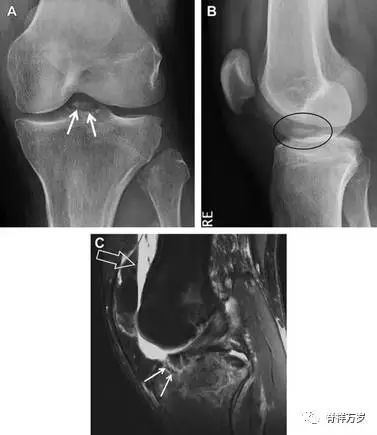

8前交叉韧带胫骨髁间嵴撕脱骨折

前交叉韧带撕脱骨折常发生在胫骨髁间嵴(图 1)。这种骨折在青少年中常见,但在成年人中也并不像大家想象的那么少见。

图 1 摩托车事故患者前交叉韧带撕脱性骨折

A 正位片示胫骨髁间嵴底部骨折(箭头),注意别把这个骨折碎片错认为关节内结构。B 侧位片示胫骨上方可见一细长型骨折碎片(椭圆)。C MRI 矢状位 T2 加权像示前交叉韧带附着于撕脱的骨折碎片上(箭头),注意周围存在骨髓水肿和积脂血征(空箭头)。